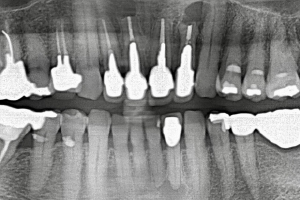

症例

ジルコニアオールセラミック

治療前

治療後

治療前のレントゲン

治療後のレントゲン

主訴は上の前歯の根元に違和感があるとのことでした。レントゲンを撮影したところ左上の2番目の歯の根元に大きな膿の袋が出来ており、保存不可能と診断、抜歯してジルコニアブリッジで治療することになりました。以前治療されていたセラミック冠の見た目も気になるとのとでした。問題のある根管治療はすべてやり直し、ファイバーコアを入れてから上下6歯をジルコニアオールセラミックで治療しました。ハグキの色も健康的になりました。

5ヶ月・25回

¥880,000